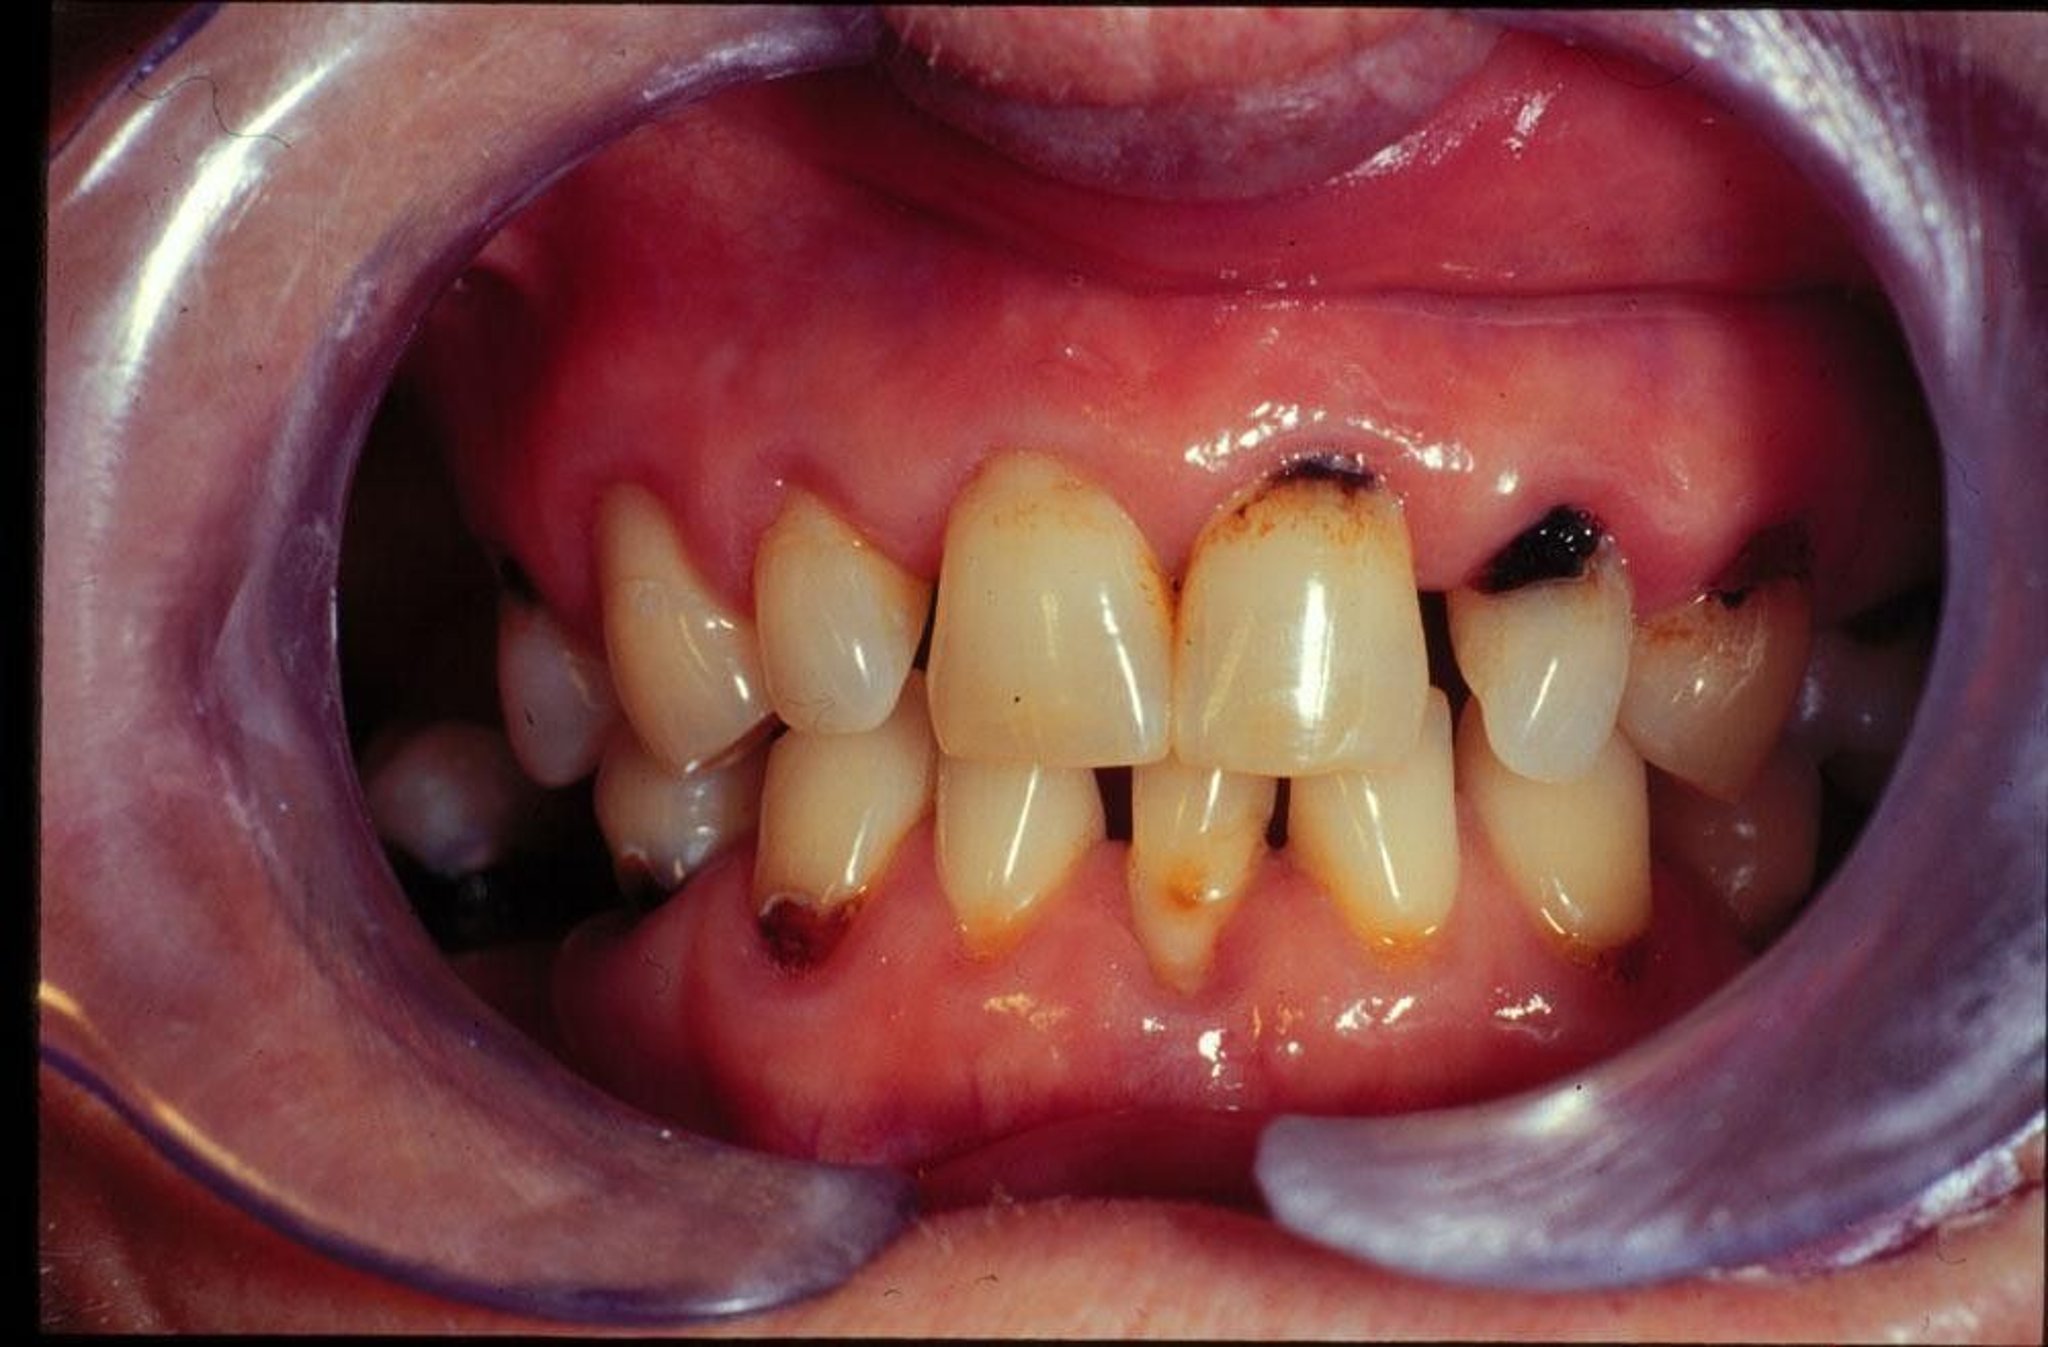

Gambar ini menunjukkan gigi berlubang yang baru dan berulang pada seseorang dengan mulut kering.

Gambar disediakan oleh Jonathan A. Ship, DMD.